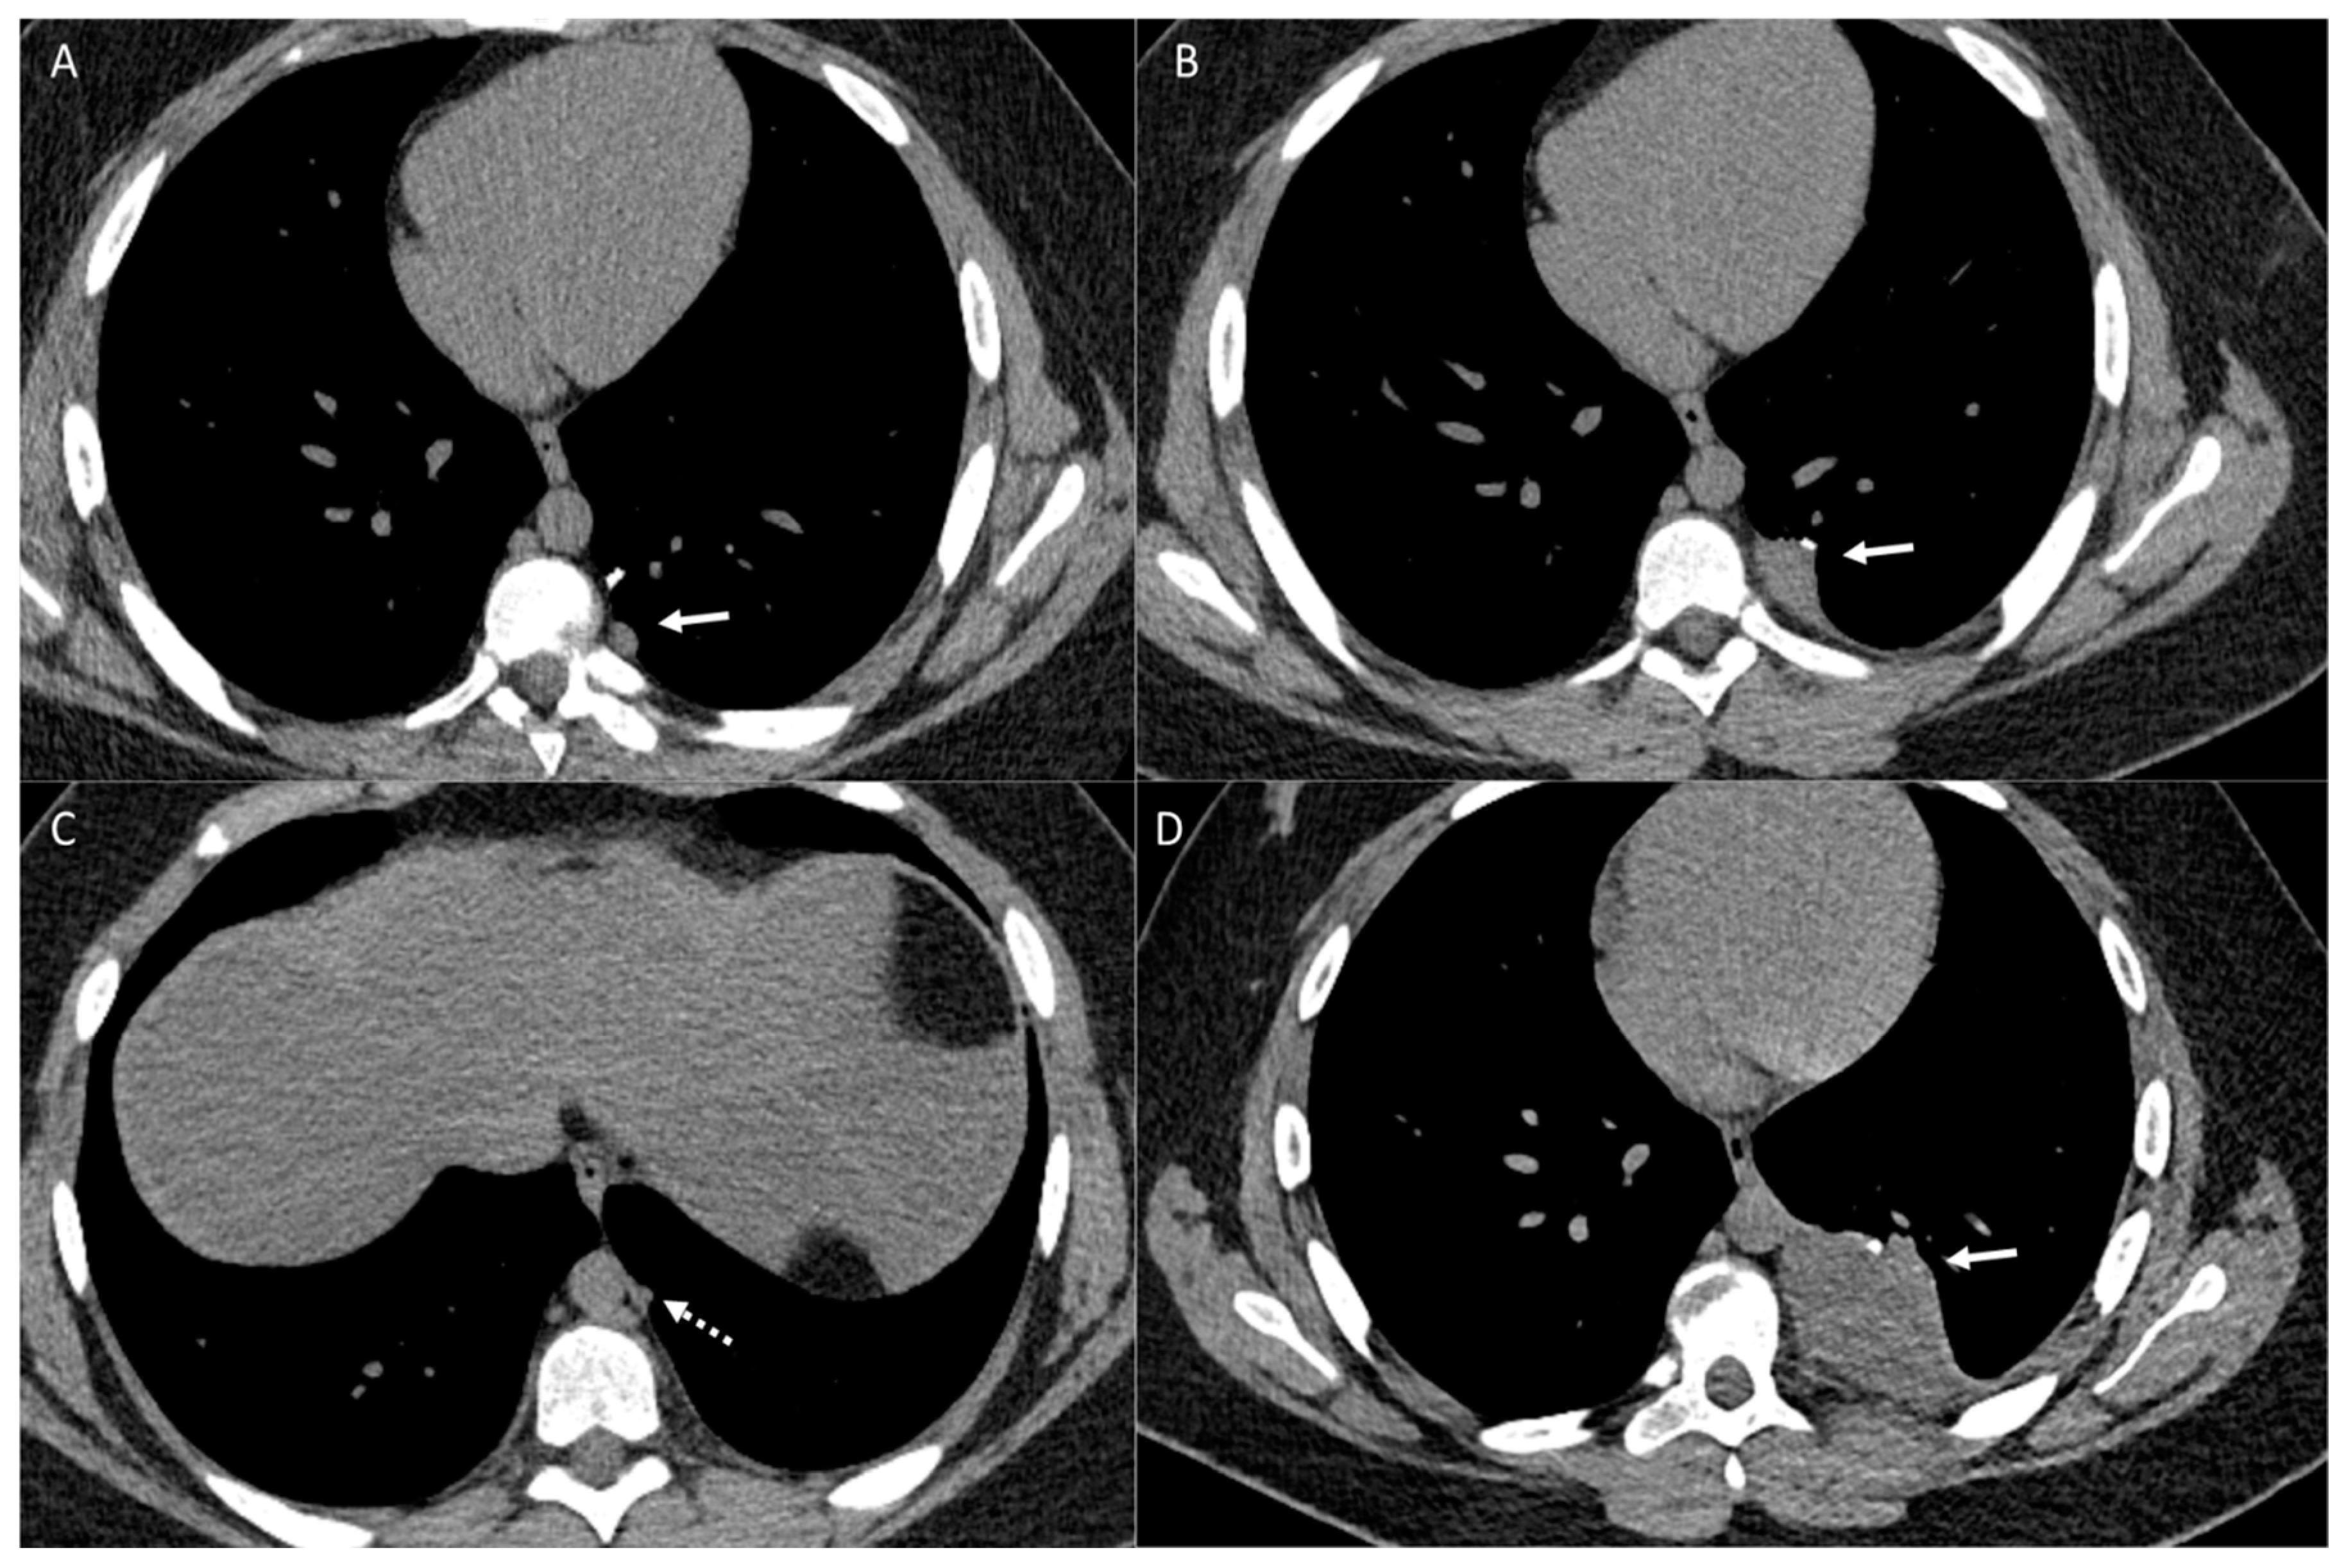

2.2. Vascular Metastasis

3. Pleura

5. Cardiac and Major Thoracic Vessels